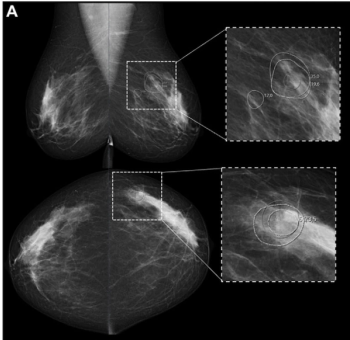

The Kaiser score offers 24 percent higher pooled specificity than the Breast Imaging Reporting and Data System (BI-RADS) for detecting malignancies on breast MRI, according to a 29-study meta-analysis.

While recalls initiated by one of two reviewing radiologists after screening mammography were nearly 10 percent higher than recalls initiated by an AI software, the AI-initiated recalls had an 85 percent higher positive predictive value for breast cancer, according to a new study.